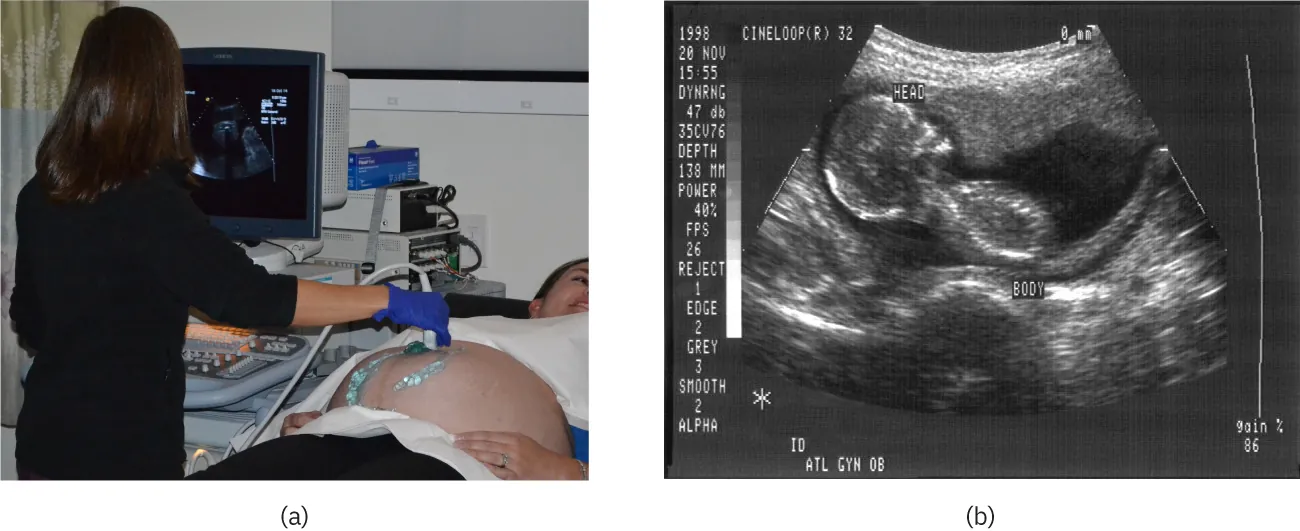

The most common ultrasound applications produce an image like that shown in Figure 17.43. The speaker-microphone broadcasts a directional beam, sweeping the beam across the area of interest. This is accomplished by having multiple ultrasound sources in the probe’s head, which are phased to interfere constructively in a given, adjustable direction. Echoes are measured as a function of position as well as depth. A computer constructs an image that reveals the shape and density of internal structures.

The first part of the diagram shows an ultrasound device scanning a woman’s abdomen. The second part of the diagram is an ultrasound scan report of the abdomen.

Figure 17.43 (a) An ultrasonic image is produced by sweeping the ultrasonic beam across the area of interest, in this case the person's abdomen. Data are recorded and analyzed in a computer, providing a two-dimensional image (credit: COD Newsroom, Flickr). (b) Ultrasound image of 12-week-old fetus. (credit: Public Health Image Library, CDC)

How much detail can ultrasound reveal? The image in Figure 17.43 is typical of low-cost systems, but that in Figure 17.44 shows the remarkable detail possible with more advanced systems, including 3D imaging. Ultrasound today is commonly used in prenatal care. Such imaging can be used to see if the fetus is developing at a normal rate, and help in the determination of serious problems early in the pregnancy. Ultrasound is also in wide use to image the chambers of the heart and the flow of blood within the beating heart, using the Doppler effect (echocardiology).